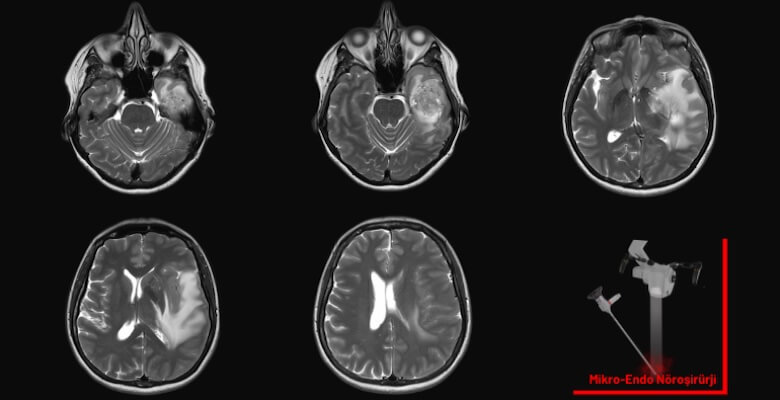

Son yıllarda beyin ve omurga cerrahisinde hasta profili belirgin biçimde değişti. Artık ameliyat masasında sadece ileri yaşlı hastalar değil, genç erişkinler de yer alıyor. Özellikle...